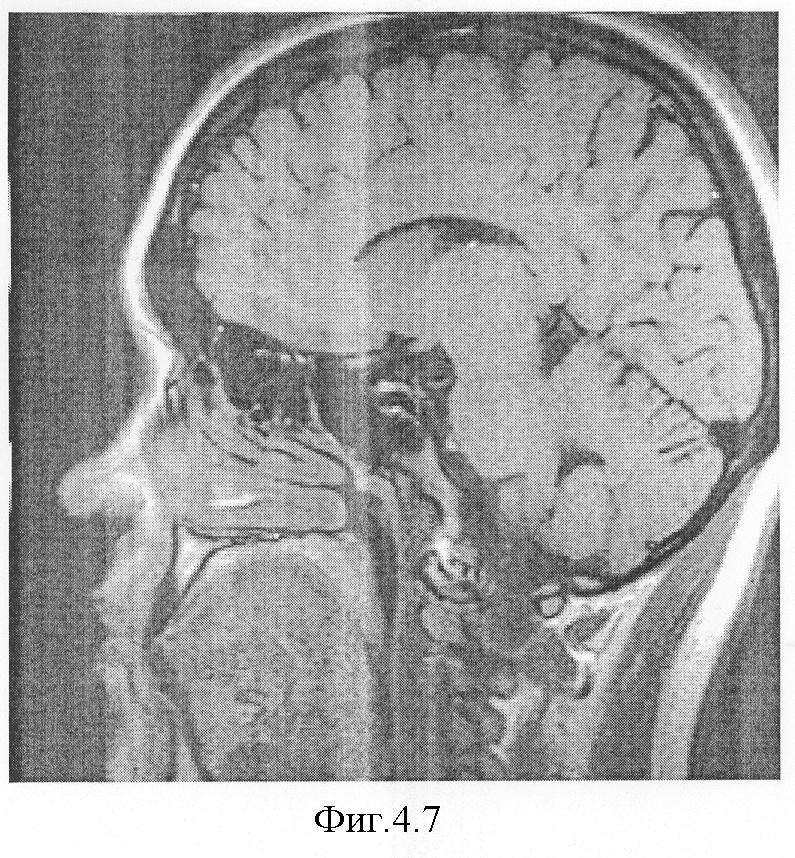

На фиг.4.1-7 показаны результирующие семь изображений, проходящие в сагиттальной плоскости через гипофиз. При этом фиг.4.1 проходит в непосредственной близости от турецкого седла справа, через сифон внутренней сонной артерии, гипофиз не затрагивает;

На фиг.4.7 видно, что срез уже проходит значительно левее турецкого седла, через сифон внутренней сонной артерии, за пределами гипофиза и, следовательно, он не обводится.